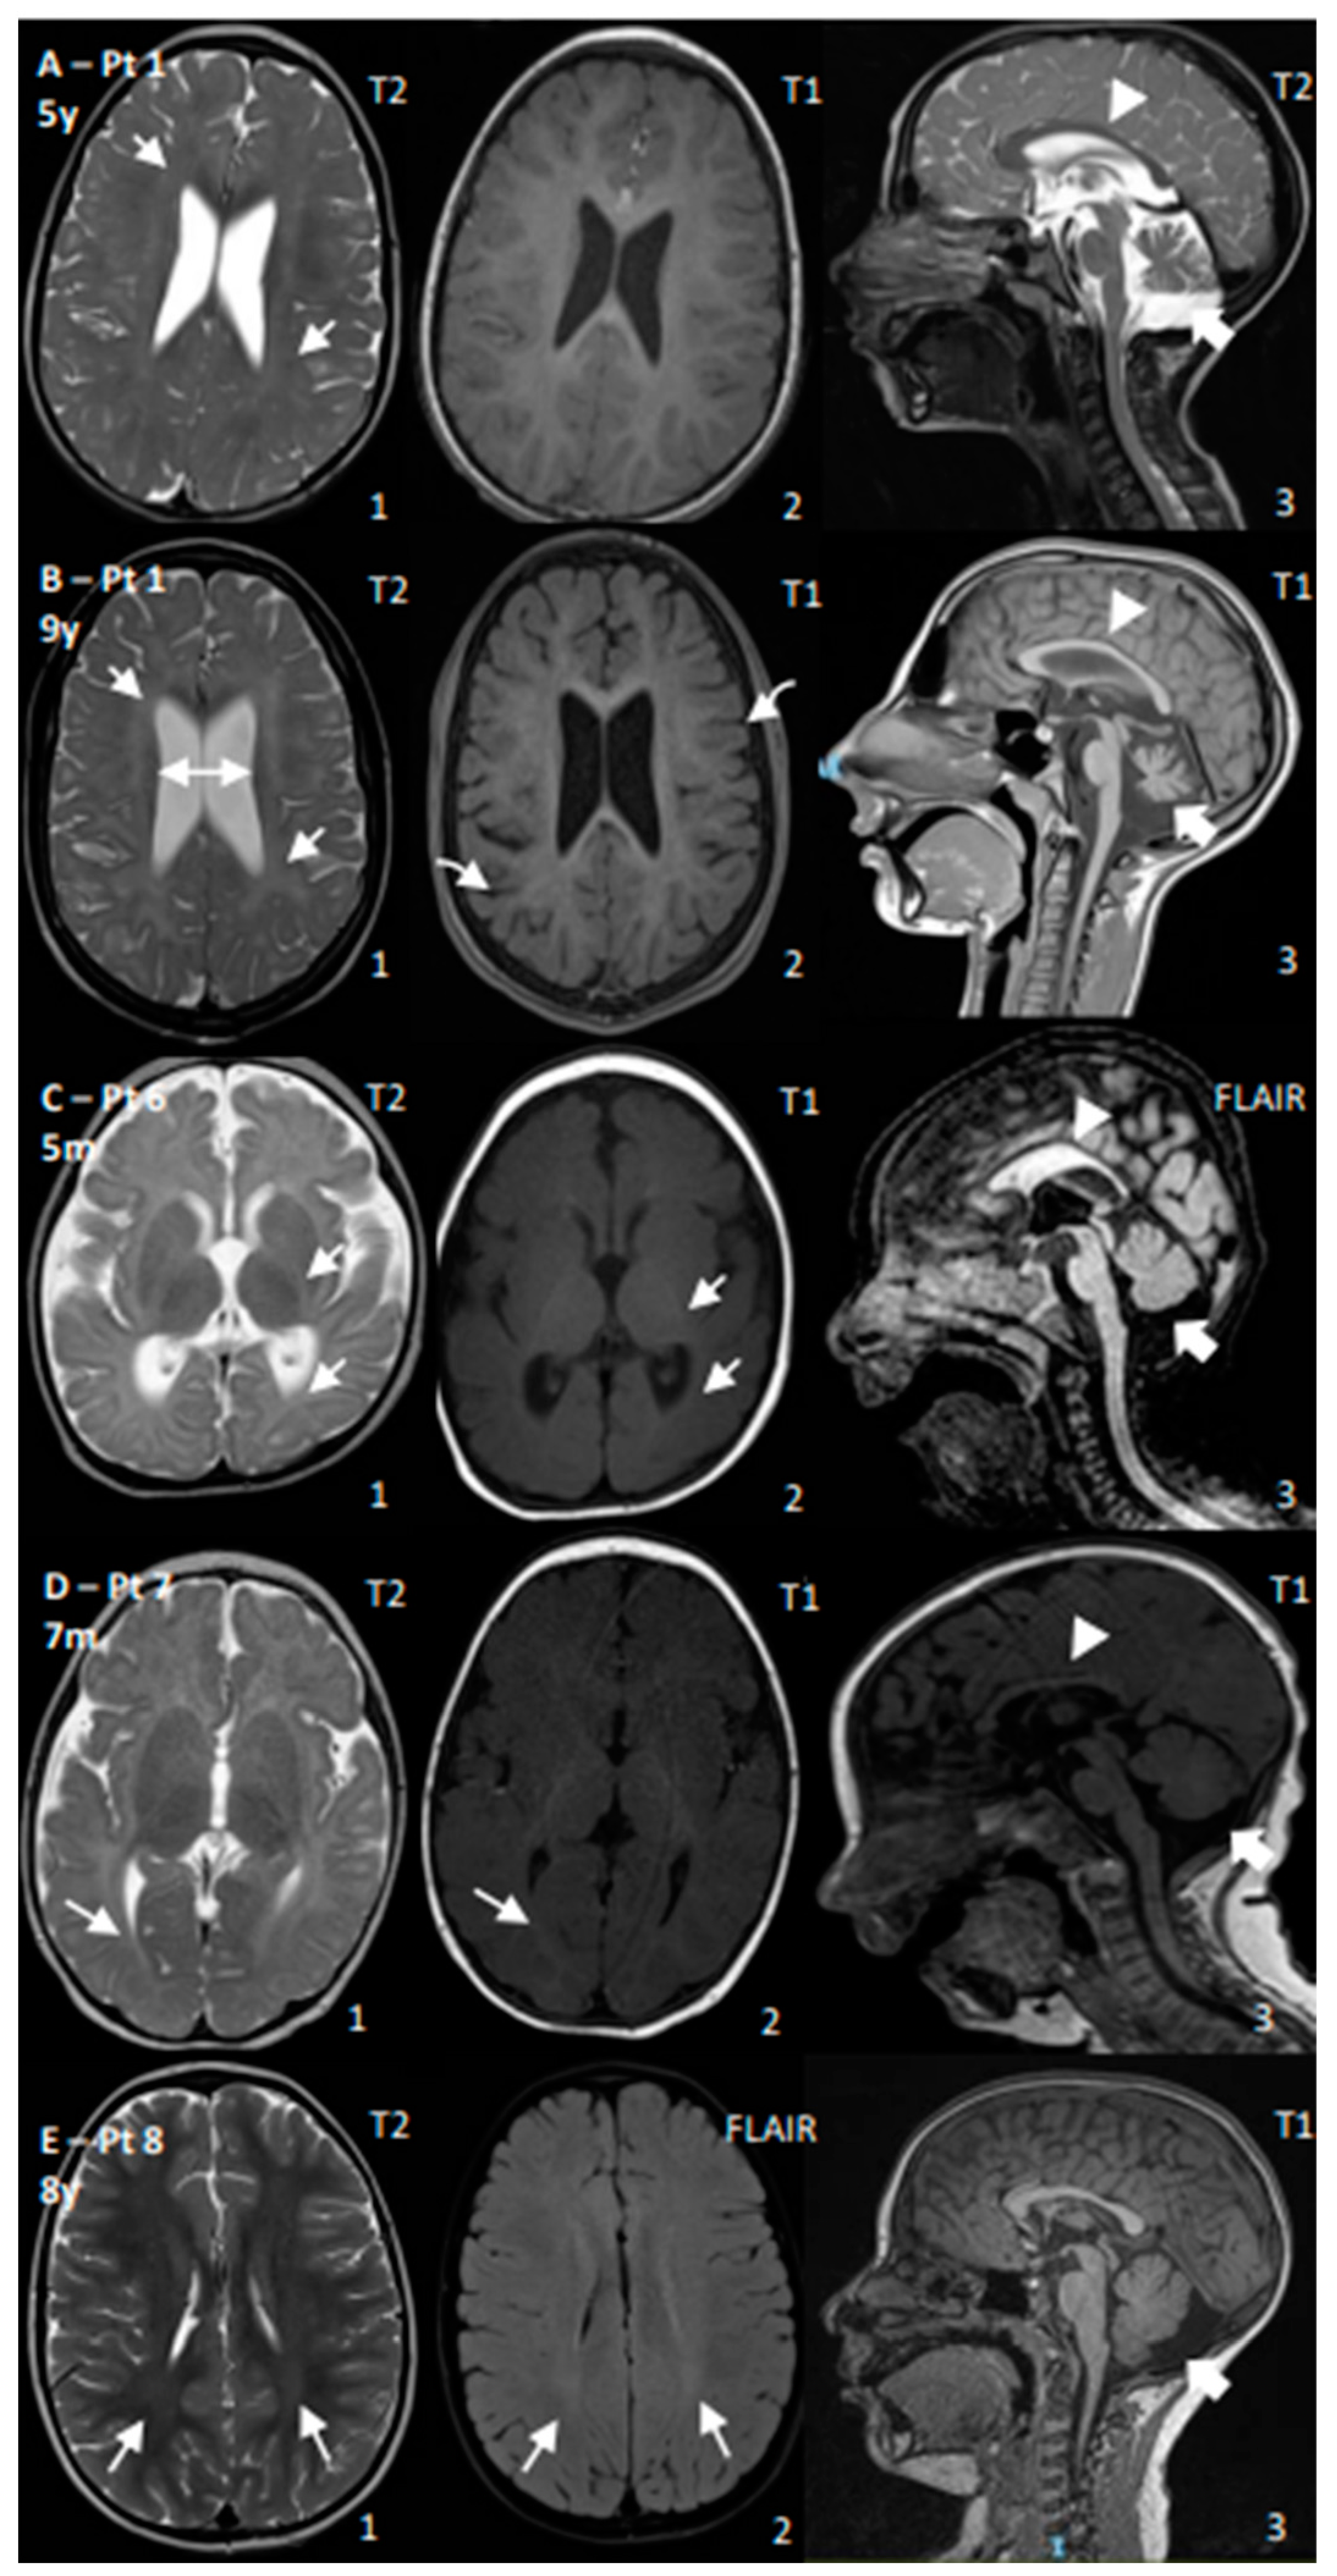

| 1 | CS I | Yes | Yes | No | Yes, −4 SD | Walk (2 y, lost 3 y) | Poor | 45 | Age: 4 y and 9 y: Progressive cerebral and cerebellar atrophy; thin CC; permanent hypomyelination | ERG: normal; VEP: increased latency; BAEP: increased I–V latency; SSEP: increased CCT |

| 2 | CS I | Yes | Yes | No | Yes, −3 SD | Walk with support (2 y) | Poor | 99–136 | Age: 10 m and 1.5 y: Progressive cerebral and cerebellar atrophy; thin CC; WM reduction and hypomyelination | NCV: normal |

| 6 | CS II | Yes | Yes | Yes | Yes, <−5 SD | No acquisition | No acquisition | N/A | Age: 5 m: Cerebral, cerebellar, CC, and WM reductions; reduced myelination for age | EEG: occipital anomalies; VEP: poor cortical definition; BAEP: increased I–V latency |

| 7 | CS II | Yes | Yes | No | Yes, <−5 SD | Head control (5 m) | Poor, then regression | 198–270 | Age 7 m: Cerebral, cerebellar, CC, and WM reductions; reduced myelination for age | NCV: demyelinating SM neuropathy; ERG: normal; VEP: high latency |

| 8 | CS III | No | Yes | No | No | Walk (1 y) | Normal | 49 | Age: 8 y: mild posterior WM T2 hyperintensity; increased posterior fossa | BAEPs: increased I–V latency; ERG/VEP: normal; NCS: mild decrease in motor conduction velocity in the lower limbs |